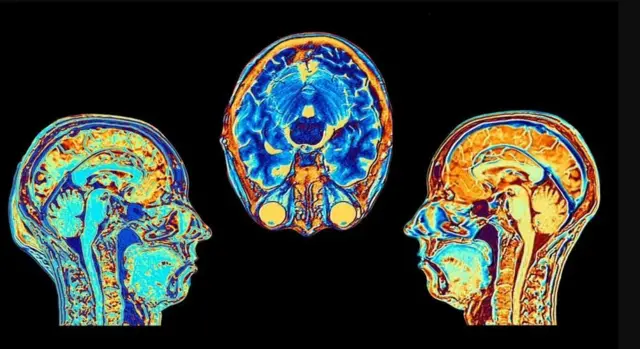

Habka isbadalka maskaxda iyo qaabka ay u shaqeyso

Maadada Coeruleus locus ( barta baluuga ah) wuxuu ku yaalaa jirridda maskaxda, meel wax yar ka sarreeya cirifka qoorta, wuxuuna ka kooban yahay ilaa 50,000 oo unug, waana qayb yar oo ka mid ah 86 bilyan ee neerfo ee habka dhexe ee neerfayaasha.